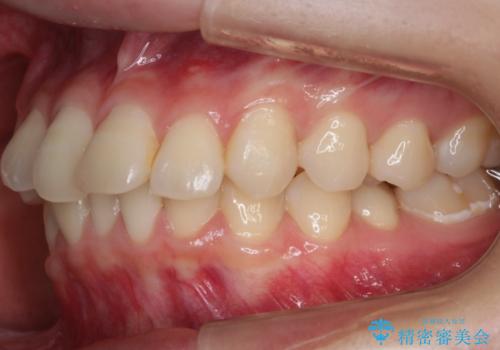

- 笑った時の歯の見え方を治したいとのことで矯正相談にいらっしゃいました。

一見そこまで大きなガタつきはないようにも見えますが、前歯の角度の不揃いや噛み合わせのズレなどから見え方に影響が出てしまっていました。

抜歯は全く必要のないレベルのガタつきだったため、マイクロインプラントを用いて歯全体を後方に移動させていくことできれいな歯並びを獲得することができました。